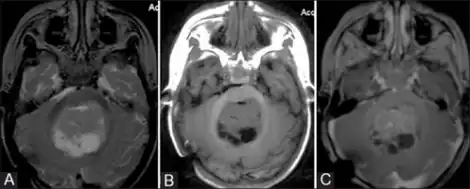

Appearance on radiologic exam

AT/RTs can occur at any sites within the CNS; however, about 60% are located in the posterior fossa or cerebellar area. The ASCO study showed 52% posterior fossa; 39% sPNET; 5% pineal; 2% spinal, and 2% multifocal.[1]

The tumors' appearance on CT and MRI are not specific, tending towards large size, calcifications, necrosis (tissue death), and hemorrhage (bleeding). Radiological studies alone cannot identify AT/RT; a pathologist almost always has to evaluate a brain tissue sample.

The increased cellularity of the tumor may make the appearance on an uncontrasted CT to have increased attenuation. Solid parts of the tumor often enhance with contrast MRI finding on T1 and T2 weighted images are variable. Precontrast T2 weighted images may show an isosignal or slightly hypersignal. Solid components of the tumor may enhance with contrast, but not always. MRI studies appear to be more able to pick up metastatic foci in other intracranial locations, as well as intraspinal locations.